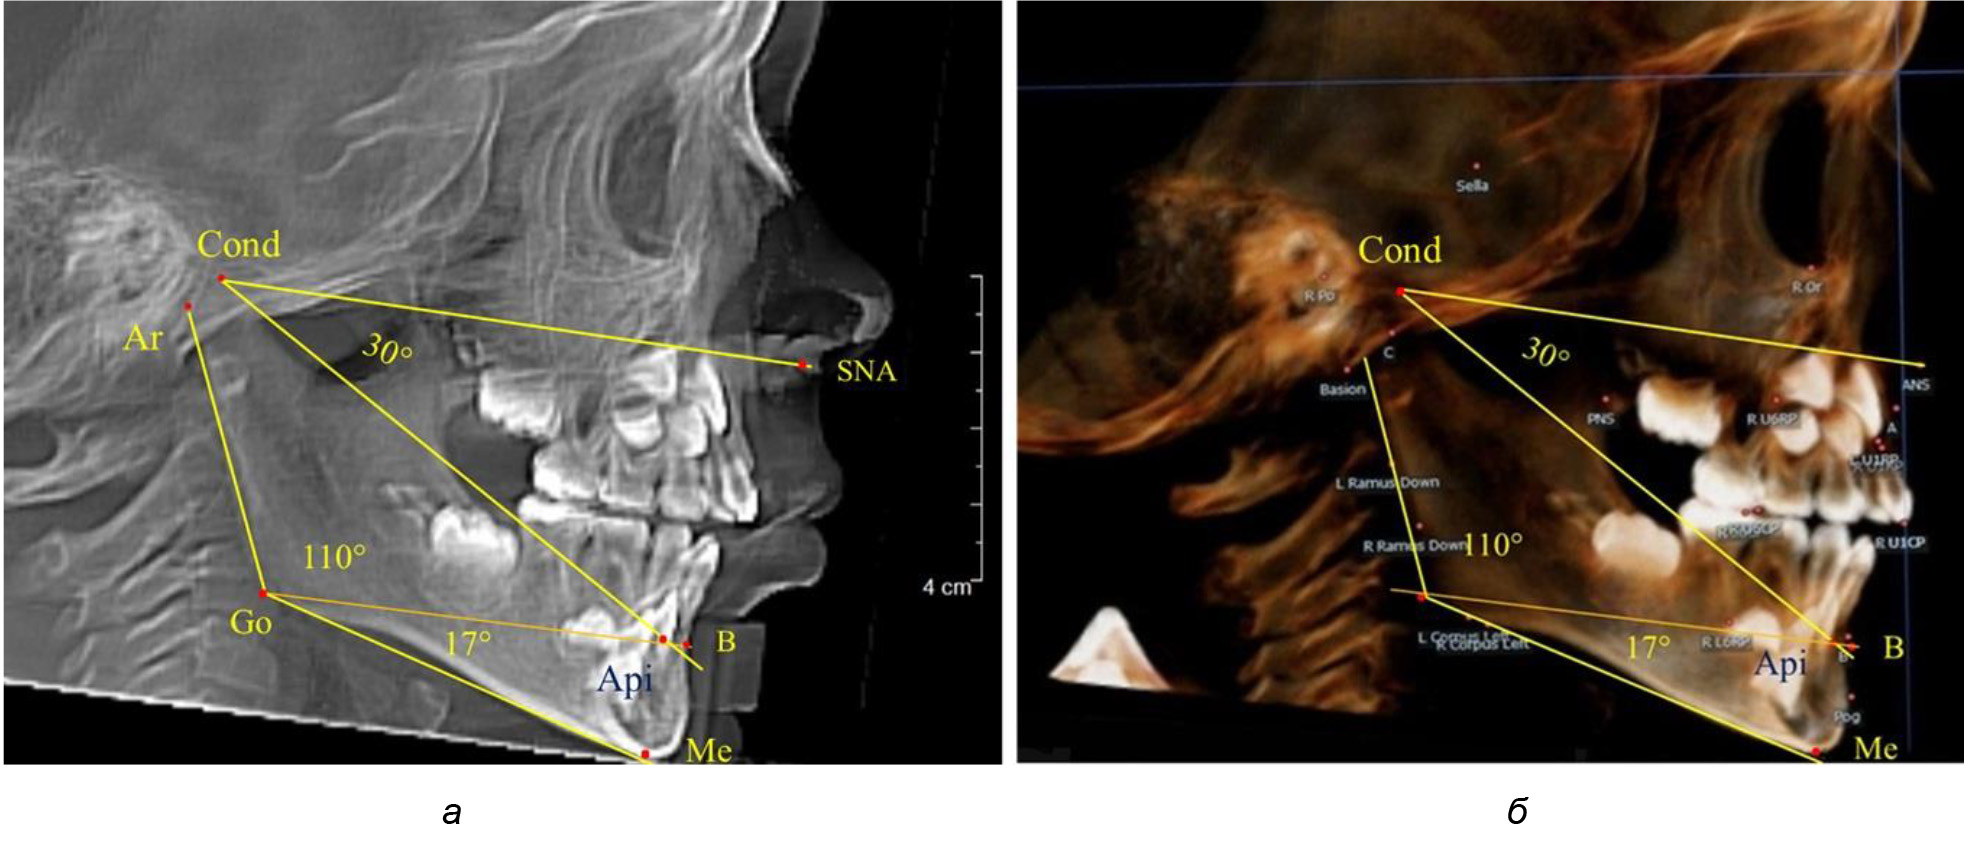

После смены всех молочных зубов (анализ 9 ТРГ) и после прорезывания вторых постоянных моляров (7 человек) происходил очередной этап подъема высоты прикуса с увеличением размеров костей гнатической части лица. Однако величина основного угла гнатической части лица SNA-Cond-Api, так же как в молочном и сменном прикусе, в норме составляла (30,02 ± 1,25)°, что не имело достоверных различий (р ˃ 0,05) с аналогичным параметром, анализируемом в других группах исследования. Угол нижней челюсти и его составляющие отличались вариабельностью параметров при различных показателях нижнечелюстного угла (рис. 6).

Рис. 6. Варианты 3D рентгенограмм детей после смены всех молочных зубов (а) и после прорезывания вторых моляров (б)

Таким образом, данные, полученные при исследовании детей с физиологическим прикусом в различные периоды онтогенеза, показали, что величина основного угла гнатической части лица SNA-Cond-Api была относительно стабильным параметром, вне зависимости от линейных параметров челюстных костей. Данный показатель может служить ориентиром для дифференциальной диагностики зубоальвеолярных и гнатических форм аномалий окклюзии в вертикальном направлении.

При анализе 16 рентгенограмм с аномалиями окклюзии в вертикальном направлении были выявлены признаки изменения основного гнатического угла. Так, для гнатических аномалий глубокой резцовой окклюзии/дизокклюзии (9 человек) отмечалось уменьшение угла гнатической части лица, величина которого была менее 26°. В то же время для гнатических аномалий (7 человек) вертикальной резцовой дизокклюзии («открытый» прикус) определялось увеличение угла гнатической части лица, который превышал значения в 33° (рис. 7).

Рис. 7. Варианты ТРГ при глубоком прикусе (а) и при открытом прикусе (б)

На представленных клинических примерах, несмотря на различия параметров основного угла гнатической части лица, определялись однотипные варианты угла нижней челюсти Ar-Go-Me и его составных частей Ar-Go-Api и Api-Go-Me.